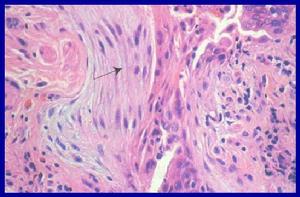

嗜酸性粒細胞性胃腸炎--病理嗜酸性粒細胞性胃腸炎在胃腸道浸潤甚廣,可從咽部至直腸,其中以胃和小腸最多見。按浸潤範圍可分為局限或瀰漫型。局限型以胃竇部最多見,肉眼所見為堅實或橡皮樣、平滑、無蒂或有蒂的息肉狀腫塊,突入腔內可導致幽門梗阻。彌溫型往往僅引起黏膜水腫、充血、增厚,偶見淺表潰瘍和糜爛。腸道病變多為彌溫型,受累腸壁水腫、增厚、漿膜面失去光澤、有纖維滲出物覆蓋。

組織學特點包括:

2、基質有大量嗜酸粒細胞和淋巴細胞浸潤,可同時伴有巨噬細胞、巨細胞或組織細胞浸潤;

3、黏膜下血管、淋巴管、肌層、漿膜和腸系膜淋巴結均可受累,伴有黏膜潰瘍與有蒂或無蒂的肉芽腫。嗜酸粒細胞浸潤可僅局限於胃腸壁,亦可呈穿壁性。

klein根據嗜酸粒細胞浸潤胃腸壁的程度分為:1.黏膜病變型:黏膜內大量嗜酸粒細胞浸潤,伴明顯的上皮細胞異常,腸絨毛可完全消失,導致失血、缺鐵、吸收不良和蛋白丟失等;2.肌層病變型:浸潤以肌層為主,胃腸壁增厚,呈結節狀,導致狹窄與梗阻塞;3.漿膜病變型:浸潤以漿膜為主,漿膜增厚,並可累及腸系膜淋巴結,有腹水形成。